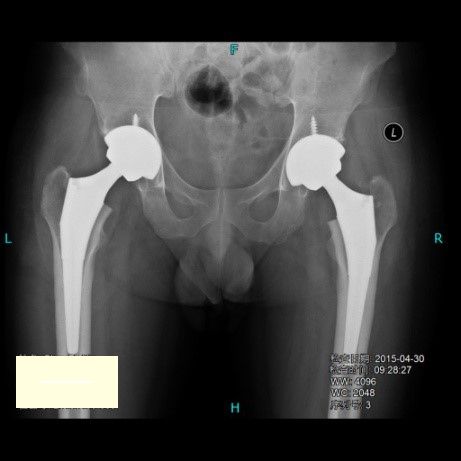

双侧人工全髋关节置换术